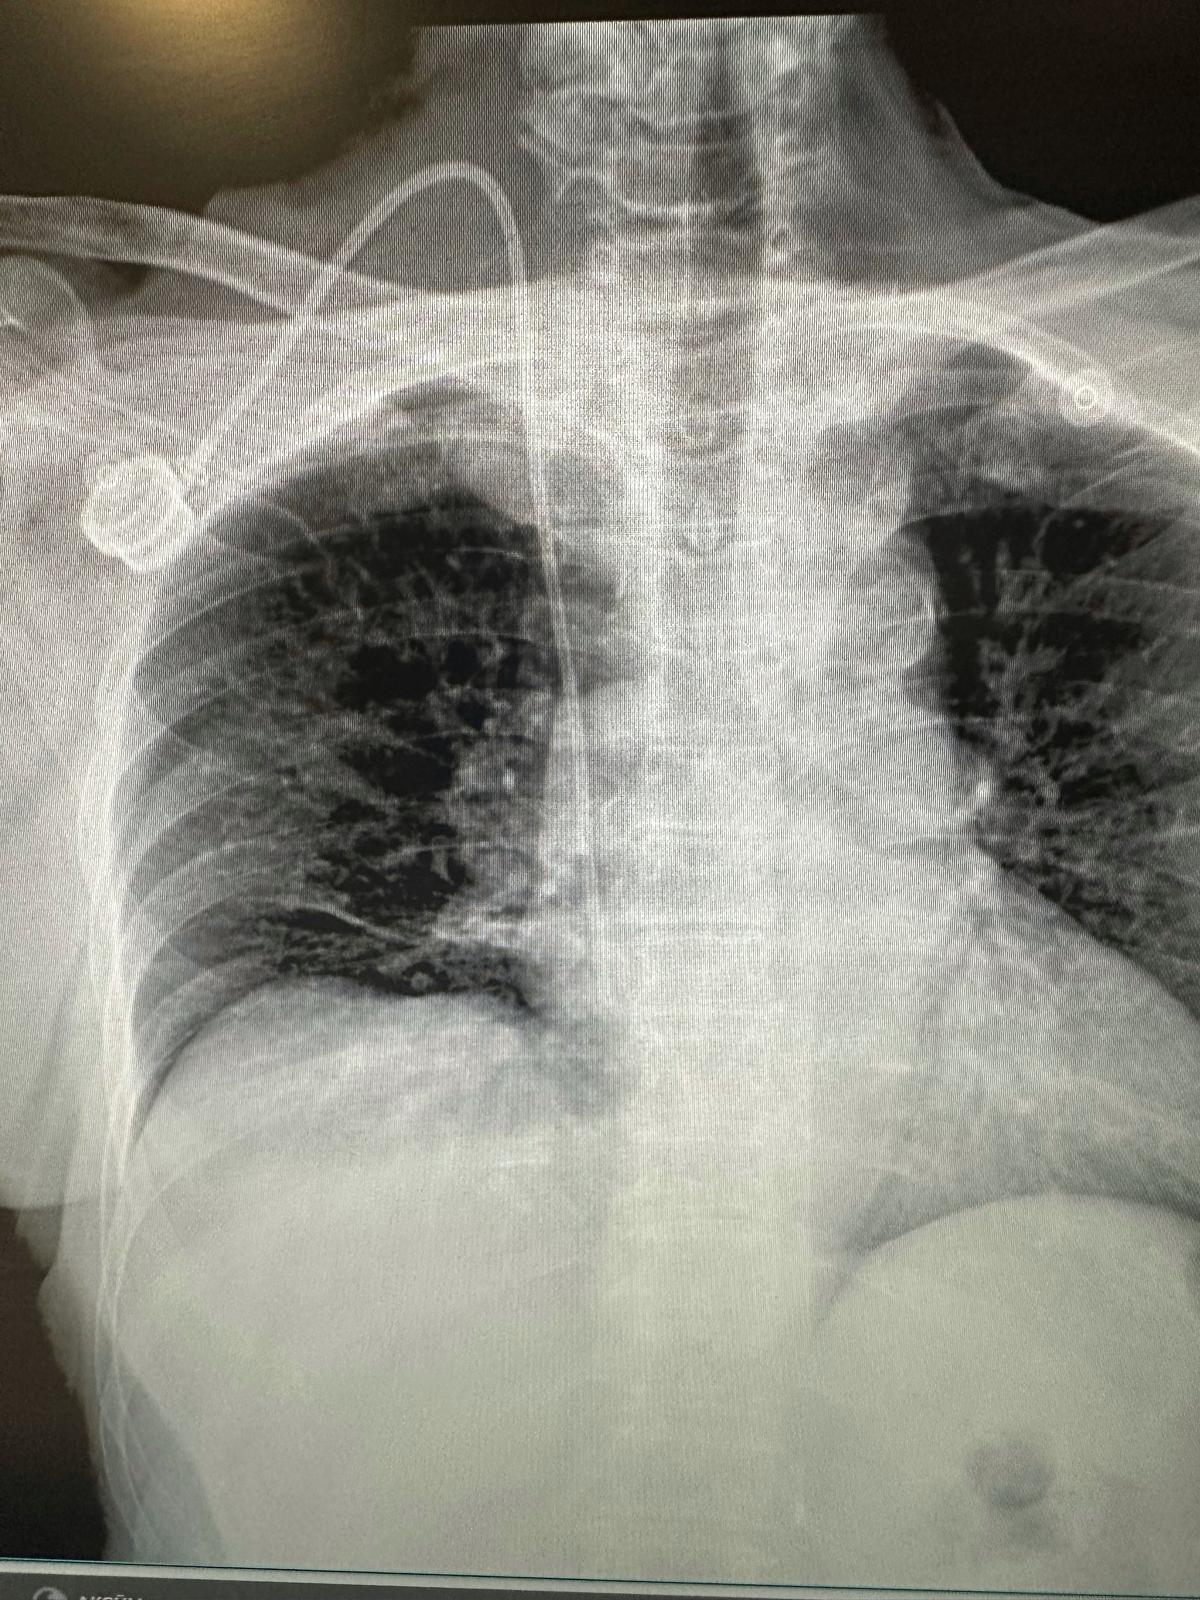

“Port kateter uygulaması, kemoterapi sürecinde yaşanan bu sıkıntıları tamamen ortadan kaldırıyor. Steril koşullarda, cilt altına küçük bir operasyonla yerleştirilen bu cihaz sayesinde ilaçlar doğrudan ana damara veriliyor. Böylece her seans öncesinde damar yolu arama ve defalarca iğne yapılma sorunu yaşanmıyor. Hastalarımız tedavilerine çok daha konforlu ve güvenli şekilde devam edebiliyor.”

Burdur Devlet Hastanesi’nde yapılan ilk port kateter uygulaması, 78 yaşındaki bir kadın hastaya başarıyla gerçekleştirildi. Operasyonun ardından hasta, kemoterapiye sorunsuz şekilde devam ederken, yeni yöntemden duyduğu memnuniyeti dile getirdi.